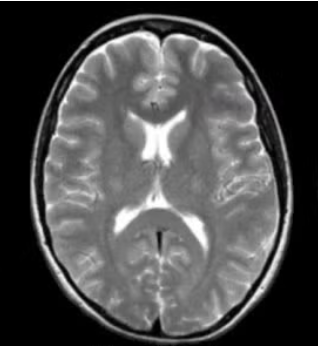

T2 weighted

Which type of CT contrast highlights fluid and pathology: water is bright, fat is bright